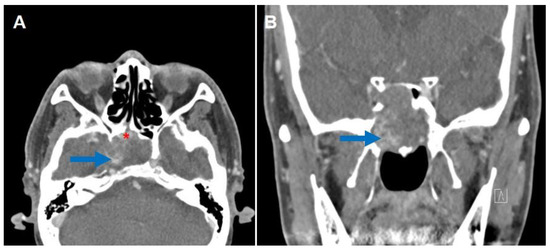

Successful Endoscopic Transsphenoidal Approach Treatment of Sphenoid Sinus Organized Hematoma Causing Visual Deficit: A Case Report

Background: Organized hematoma in the sphenoid sinus is rare, but serious complications, such as visual deficits, can occur. Three such case reports have been published previously in the literature; however, none have achieved complete recovery of the vision. Case presentation: A [...] Read more.

Background: Organized hematoma in the sphenoid sinus is rare, but serious complications, such as visual deficits, can occur. Three such case reports have been published previously in the literature; however, none have achieved complete recovery of the vision. Case presentation: A 69-year-old male patient was referred to the ear, nose, and throat department with an expansile soft tissue mass filling the right sphenoid sinus and blurry vision in his right eye. Complete mass removal was achieved by a wide opening of the sphenoid sinus via an endoscopic transsphenoidal approach, followed by cauterization of the feeding artery and coverage by a nasoseptal flap. The patient’s vision was restored after the operation, and he declared no visual symptoms until the latest follow-up (one year after the surgery). Conclusions: Complete excision with an endoscopic endonasal transsphenoidal approach can restore visual deterioration caused by a sphenoid sinus organized hematoma. Full article